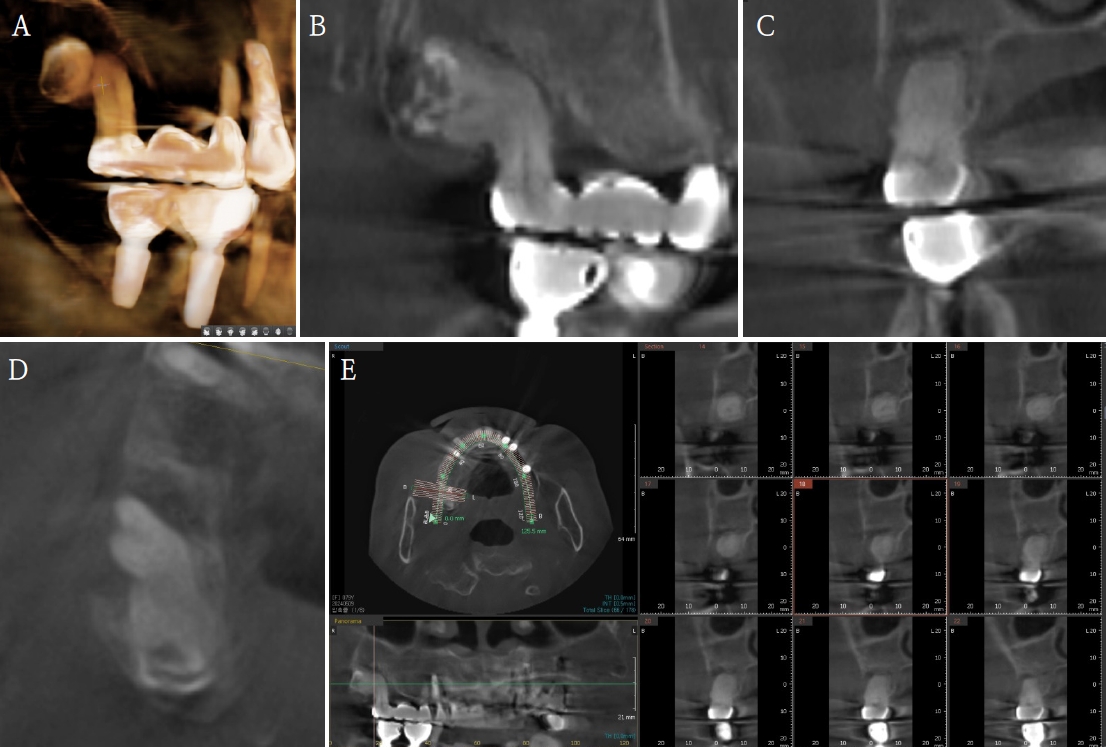

이번 내원 시 촬영한 파노라마방사선사진에서 우측 상악 제2대구치의 치근단 주위까지 진행된 수직 골결손이 관찰되어 동 치아의 발치를 계획하였다(Fig. 1A). 12년 전 초진 방사선영상과 마찬가지로 제3대구치가 근접하였고 그 위치가 움직이지 않았으므로 두 치아 관계의 자세한 분석을 위하여 CBCT(PHT-65LHS, Vatech, Hwaseong, Korea)를 촬영하였다(Fig. 2). CBCT는 94kVp, 8mA, 536x536x300pixels의 조건에서 촬영하여 FOV 161x90mm의 영상을 획득하였다. CBCT 영상에서 제2대구치와 제3대구치의 근접한 치근 부위는 주변 상아질보다 약간 낮은 방사선 흑화도를 보이는 부위가 관찰되었고 치근은 구근상을 보여 과백악질증의 소견을 확인할 수 있었으며, 그 부위의 백악질이 유합된 것으로 판단하여 유합으로 잠정 진단하였다.

A. Cone-beam computed tomographic 3-dimensional reconstruction image. B. Panoramic view. C. Cross-sectional view. D. Axial view. E. Cross-sectional image shows that the two teeth are attached to each other and the roots have a bulbous appearance due to hyperproliferated cementum.

유합은 치관이 형성된 후 발생하므로 치관부가 정상적으로 관찰되어 임상적으로 진단이 쉽지 않다. 다양한 각도에서 촬영된 방사선사진에서도 유합된 두 치아가 단지 겹쳐 있는 것으로 오인하기 쉽다. 이 증례에서도 발거된 치아의 치근단방사선 사진을 통해 두 치아 사이에 치간골이나 치주인대가 존재하지 않는 것을 확인할 수 있었다(Fig. 3B). 이전의 연구들은 술 전 방사선사진이나 유합치의 발치 후 임상사진을 위주로 보고하였으나[9-12], 최근 술 전 CBCT가 포함된 유합치 진단의 증례가 보고되었다[7,8]. 그러나 국내에서 보고된 증례는 거의 없어 이번 증례에서 유합치의 술 전 CBCT영상을 평가하고, 발치 후 유합치의 유합 부위를 조직학적으로 평가하였다. 한 방향만이 아닌 여러 방향으로 관찰할 수 있는 CBCT는 유합치를 발견할 수 있는 확률을 높인다. 백악질은 과백악질증으로 인하여 두꺼워지는 경우가 아니면 CBCT에서 관찰하기 용이하지 않으며, 이는 치근을 이루고 있는 상아질과 다른 방사선학적 흑화도를 보이는 층(layer)으로 관찰되는 것으로 보고되었다[14]. 과백악질증이 없는 치아의 융합은 상아질과 백악질의 방사선학적 흑화도의 유사성 및 백악질의 매우 얇은 구조(치경부 16∼60㎛, 치근단부 150∼200㎛)로 인하여 CBCT에서도 유합과 구별이 어려운 한계가 있다. 본 증례의 경우 CBCT에서 상악 우측 제2대구치와 제3대구치의 과백악질증으로 인해 두꺼워진 백악질이 서로 붙어있는 것으로 확인되었다(Fig. 2). 술 전 CBCT 관찰을 통해 발거할 두 치아의 유합을 더 정확하게 예측하였고, 이에 발치 시 유의하여 상악결절의 파절, 두 치아의 분리, 치아의 부분적 파절 없이 발치를 시행하였다. 발거된 치아의 조직학적 검사에서 두 치아 사이에 백악질이 관찰되어 유합을 확진하였다(Fig. 4).